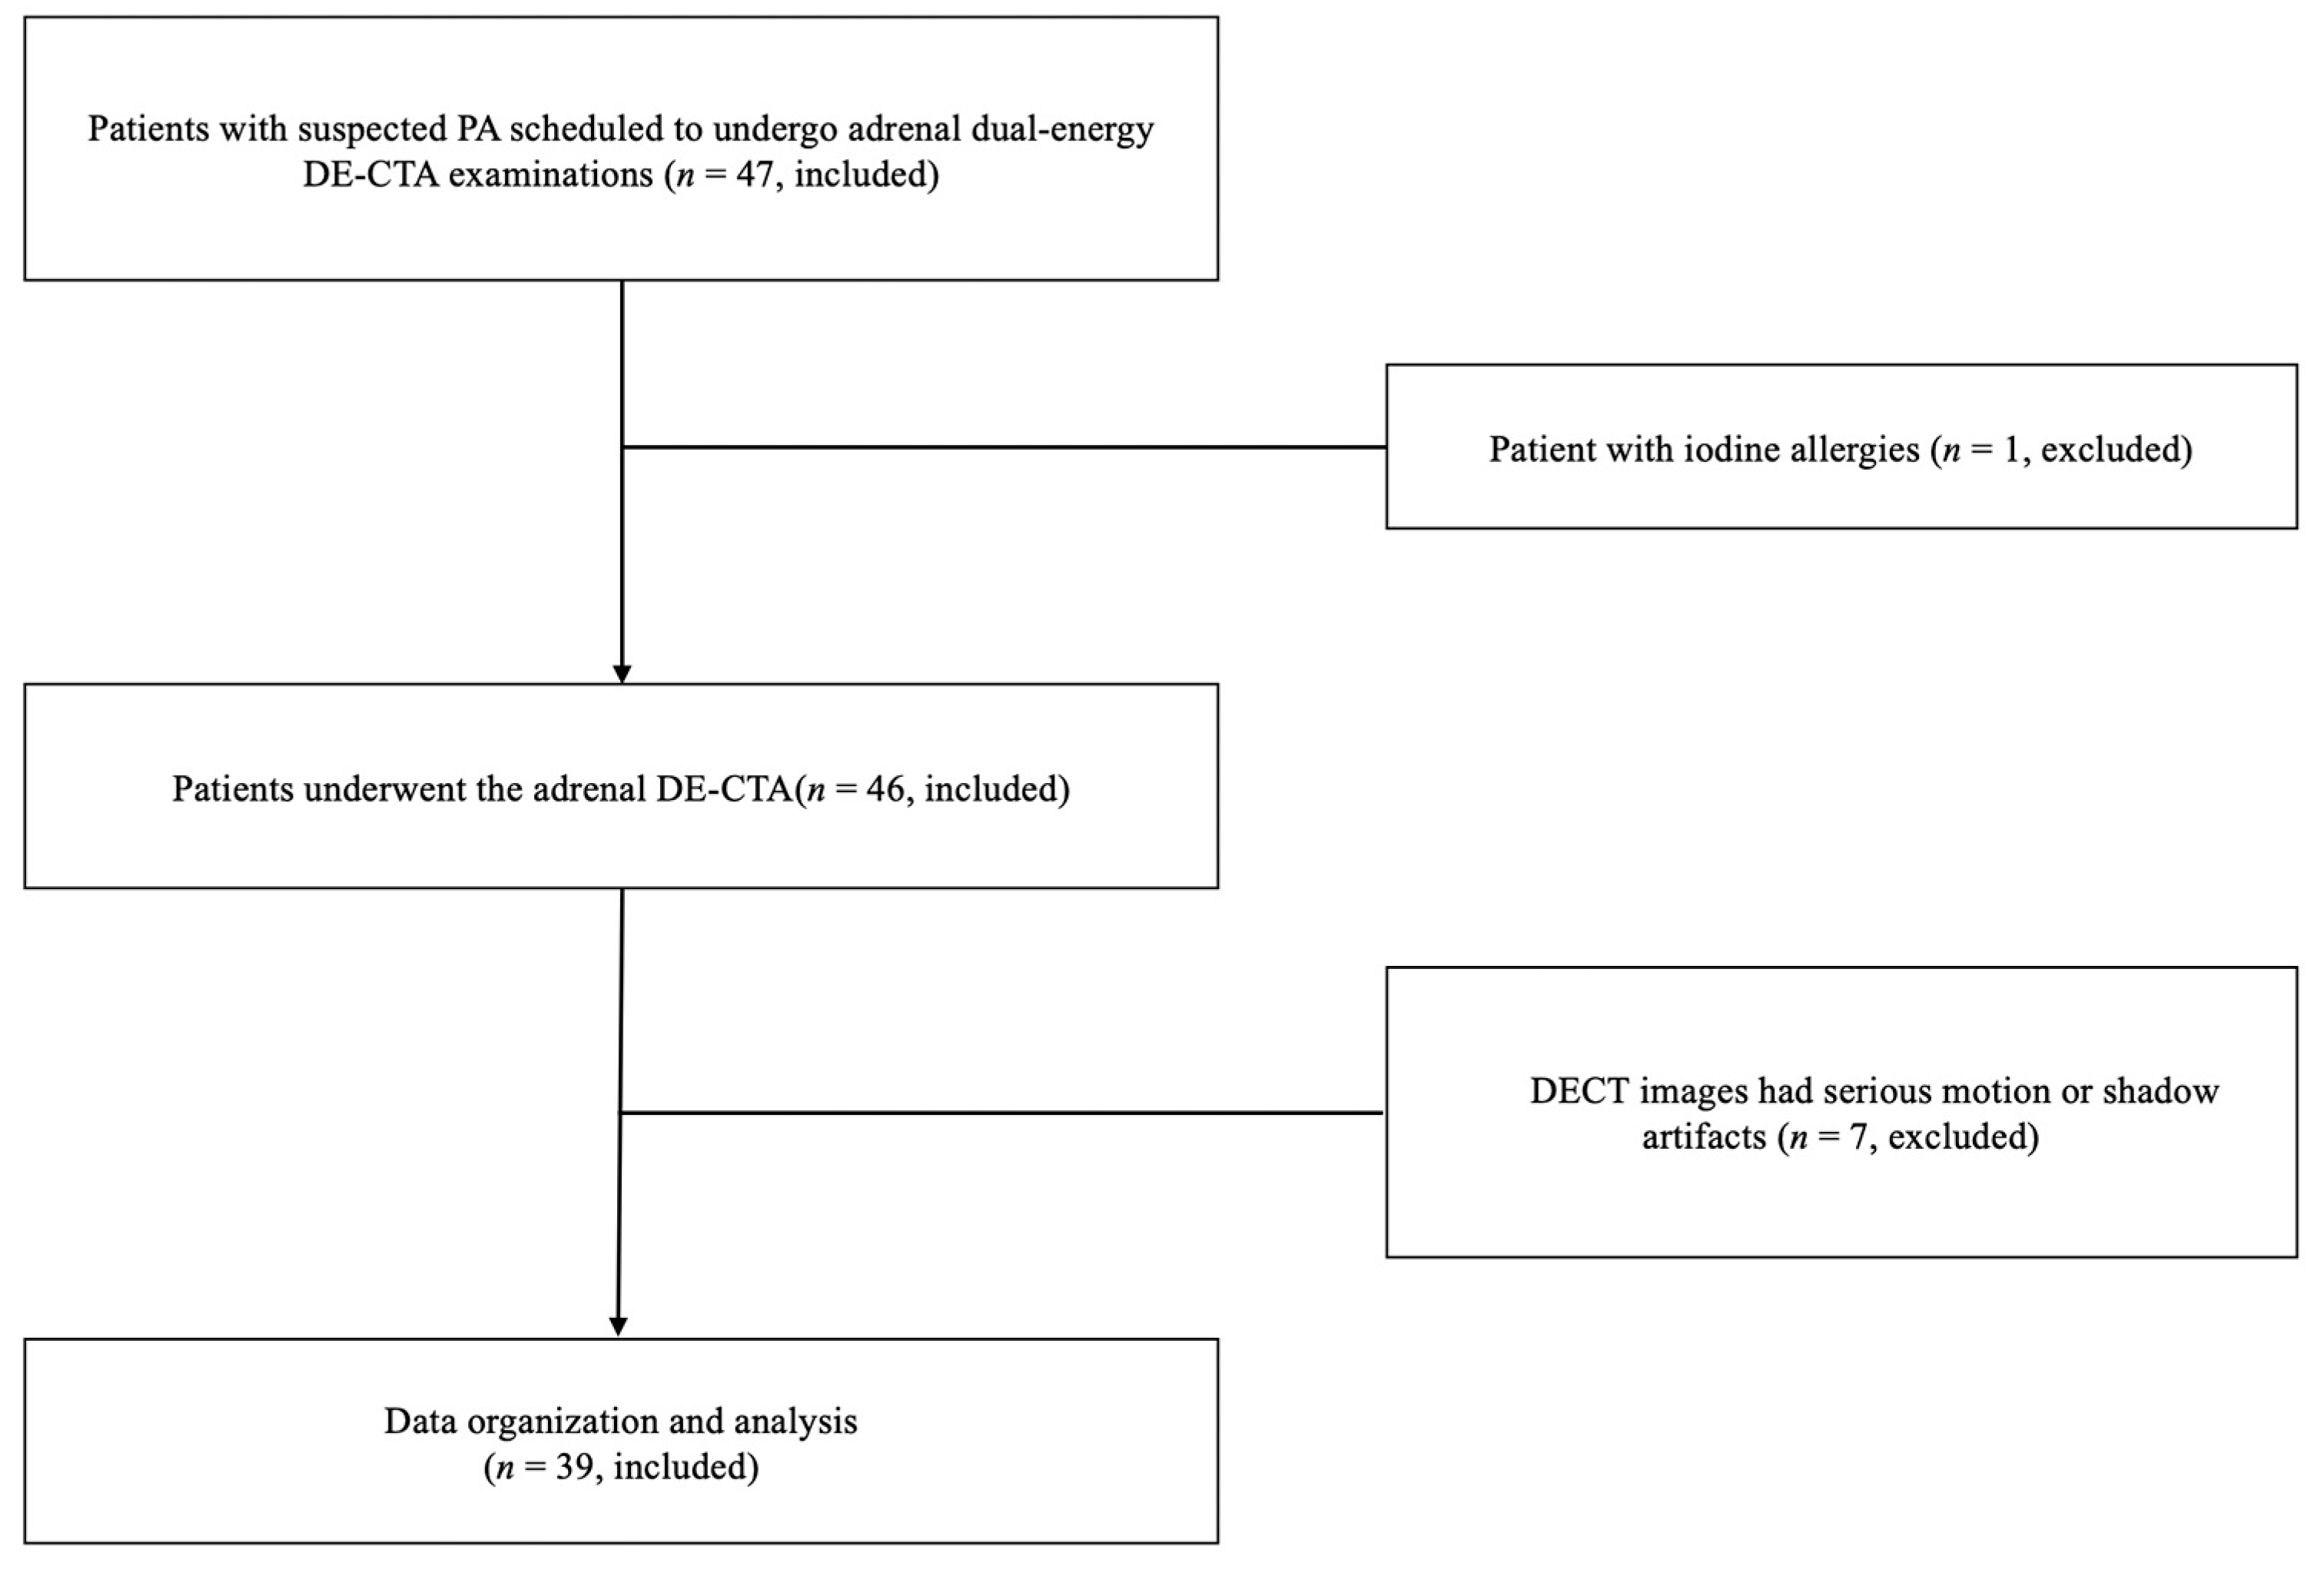

2.1. Patients